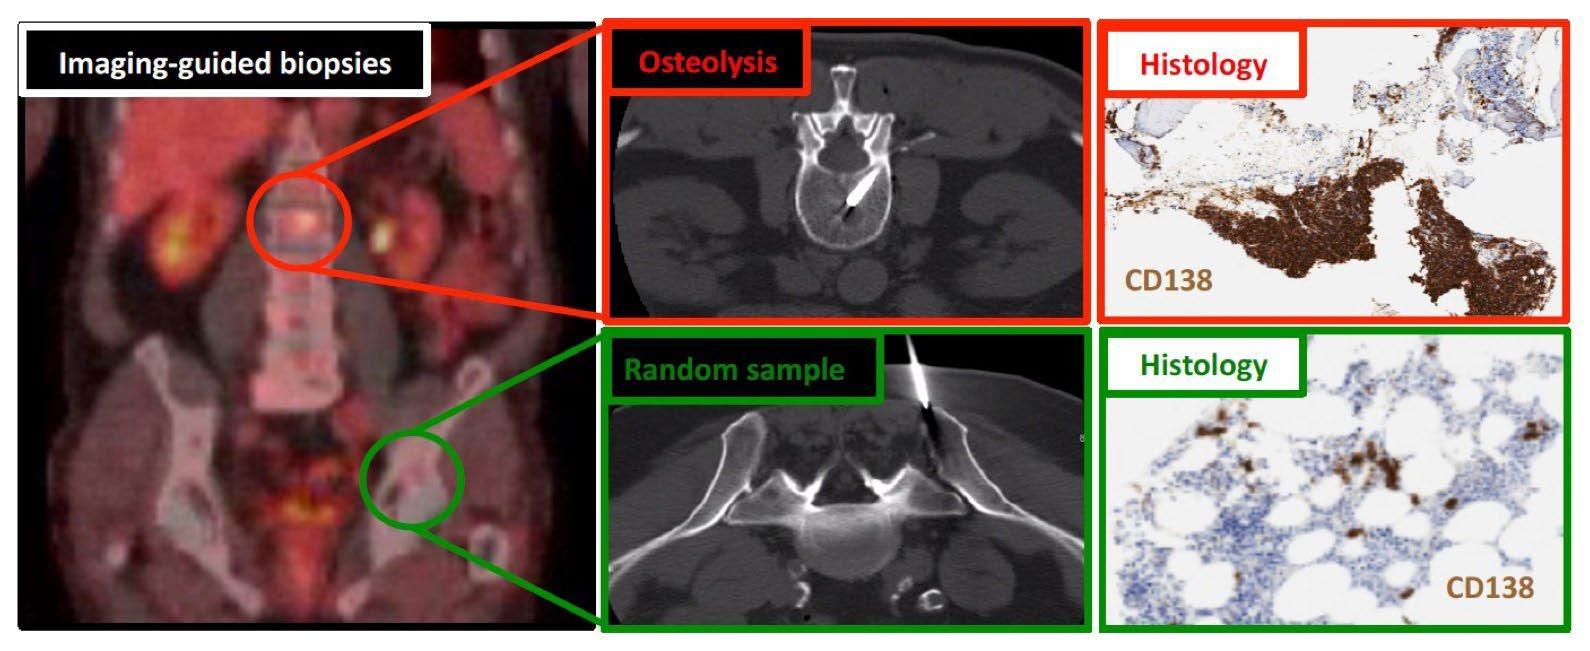

Guidelines for Diagnosis

Imaging

Hillengass 2019 Lancet Oncol, Rome 2017 Clin J Oncol, Faiman 2014 Clin Lymphoma Myeloma Leuk, Dimopoulous 2009 Leukemia